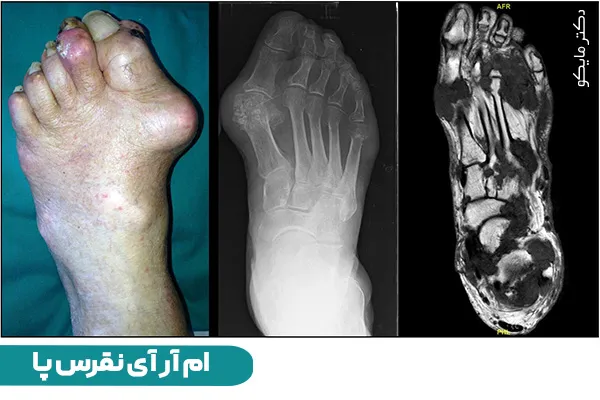

نقرس نوعی آرتریت التهابی است که میلیونها نفر را در سراسر جهان به خود مبتلا میکند. این بیماری با درد ناگهانی و شدید، قرمزی و تورم در مفاصل، به ویژه در پاها مشخص میشود. در این مقاله با دکتر مایکو همراه باشید تا به بررسی علل، علائم و درمانهای موثر نقرس در پا، دست، زانو و مچ بپردازیم.

نقرس نوعی آرتریت است که با تجمع کریستالهای اسید اوریک در مفاصل رخ میدهد. اسید اوریک یک ماده زائد است که به طور معمول از طریق کلیهها دفع میشود. با این حال، در افراد مبتلا به نقرس، بدن اسید اوریک را بیش از حد تولید میکند یا نمیتواند آن را به درستی دفع کند. در نتیجه کریستالهای اسید اوریک در مفاصل تجمع مییابند که منجر به التهاب و درد شدید میشوند.

علائم نقرس پا میتواند ناتوانکننده باشد و به طور قابل توجهی بر کیفیت زندگی فرد تأثیر بگذارد. علائم شایع شامل درد ناگهانی و شدید، قرمزی، تورم و حساسیت در مفصل آسیب دیده است. این درد اغلب به عنوان یک احساس ضرباندار یا طاقت فرسا توصیف میشود که راه رفتن یا حتی پوشیدن کفش را دشوار میکند. نقرس اغلب شست پا را درگیر میکند، اما میتواند در سایر مفاصل پا مانند مچ پا و زانو نیز رخ دهد.